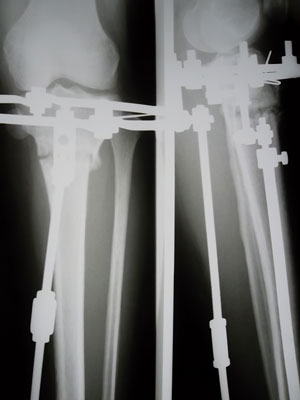

Костная мозоль зреет хорошо, к концу месяца можно приезжать на снятие аппаратов.

У Вас по 2 спицы в каждом кольце осталось???

SAM_4391.JPG

SAM_4389.JPG

Да, у меня на каждой ноге по две спицы, я хорошо себя чувствую, легче двигаюсь и намного легче поднимаюсь по лестнице)))) solnce solnce solnce

Я так рада, что снимки все же пришли))))